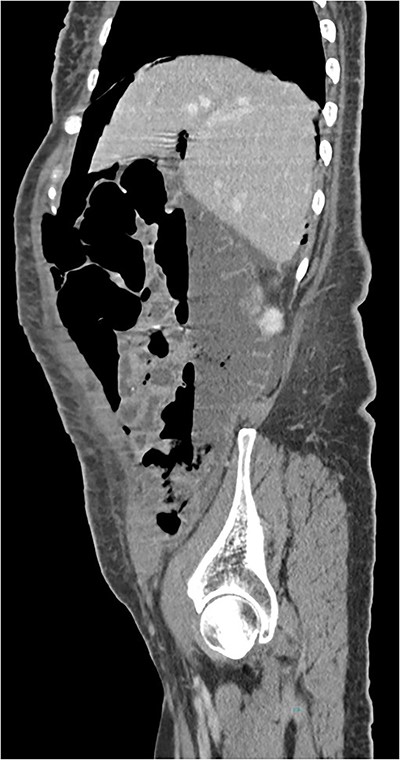

A 63-year-old woman underwent an elective hysterectomy and bilateral adnexectomy due to a large right adnexal mass (290 × 190 mm). On the sixth postoperative day, she developed nausea and vomiting, along with abdominal distension and generalized abdominal pain, without peritoneal signs or guarding. An abdominal X-ray was requested, which showed pneumoperitoneum and multiple air-fluid levels in the small intestine. Blood tests were unremarkable. An abdominal and pelvic computed tomography (CT) scan was also performed, revealing “pneumoperitoneum in a quantity above what would be expected given the postoperative timeline, with no image suggestive of hollow viscus or vaginal cuff dehiscence.” (Figs 1 and 2). Based on the clinical findings, a conservative approach was chosen. A nasogastric tube was placed, and the patient was put on a nil-by-mouth diet. Two days later, she began an oral diet and resumed intestinal transit, maintaining a favorable clinical course for the remainder of her hospital stay.